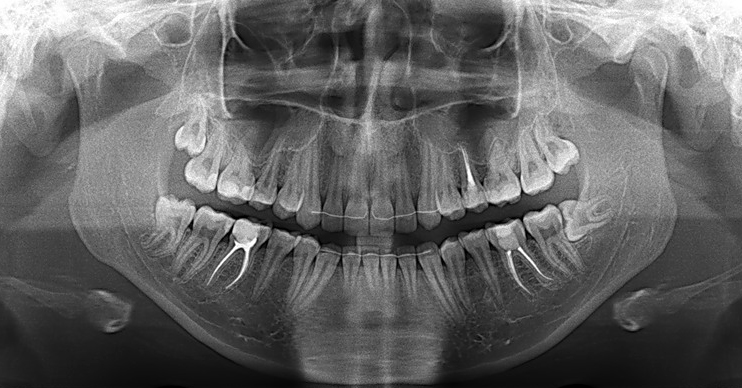

Стоматологические Исследования: Рентген Инвагинации Зубов